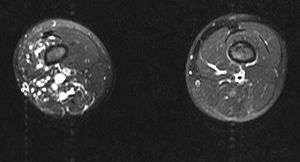

| MRI | |